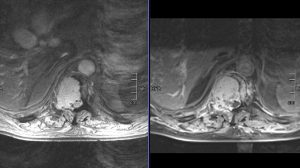

Ο απεικονιστικός έλεγχος με μαγνητική και αξονική τομογραφία της σπονδυλικής στήλης ανέδειξε μάζα κυρίως στο σώμα του 10ου θωρακικού σπονδύλου (Θ10) με περιβρογχισμό και πίεση επί του νωτιαίου μυελού. (Σημειώστε και τη διήθηση του Θ9 σπονδύλου, χωρίς οστεόλυση).

Διενεργήθη αποσυμπίεση του νωτιαίου μυελού μέσω πεταλεκτομίας και αφαίρεσης του ενδοκαναλικού τμήματος του όγκου και στη συνέχεια διαδερμική σπονδυλοδεσία με έγχυση οστικού τσιμέντου στα σπονδυλικά σώματα Θ9-Θ11